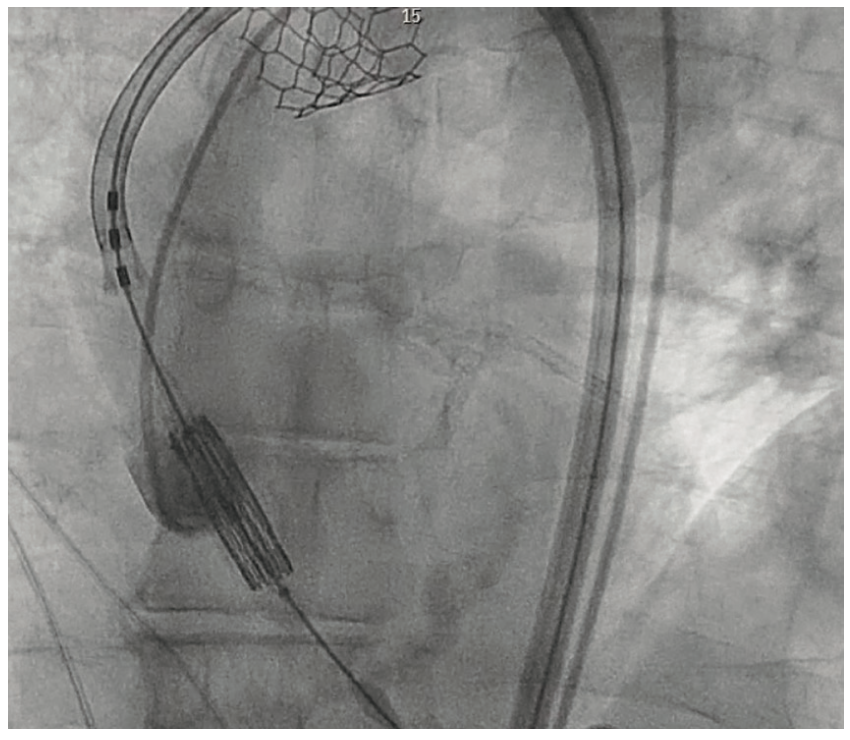

A Case of TAVR Through Subclavian Access, Complicated by Valve Tavr Valve Embolization Aortic valve replacement (avr) is the only effective therapy. Transcatheter valve embolization and migration (tvem) are potential complications of transcatheter aortic valve implantation (tavi) (1). Aortic stenosis (as) is the most common valvular heart disease. Embolization of transcatheter aortic valve replacement (tavr) prostheses is a rare and serious procedural complication. Aortic stenosis (as) is a common valvular heart disease, especially. Tavr Valve Embolization.